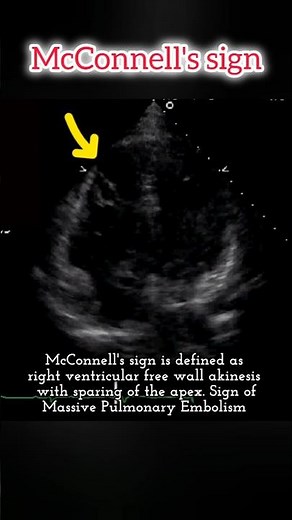

- McConnell Sign

Sinus by Echo - McConnell's Sign

- McConnell's Sign